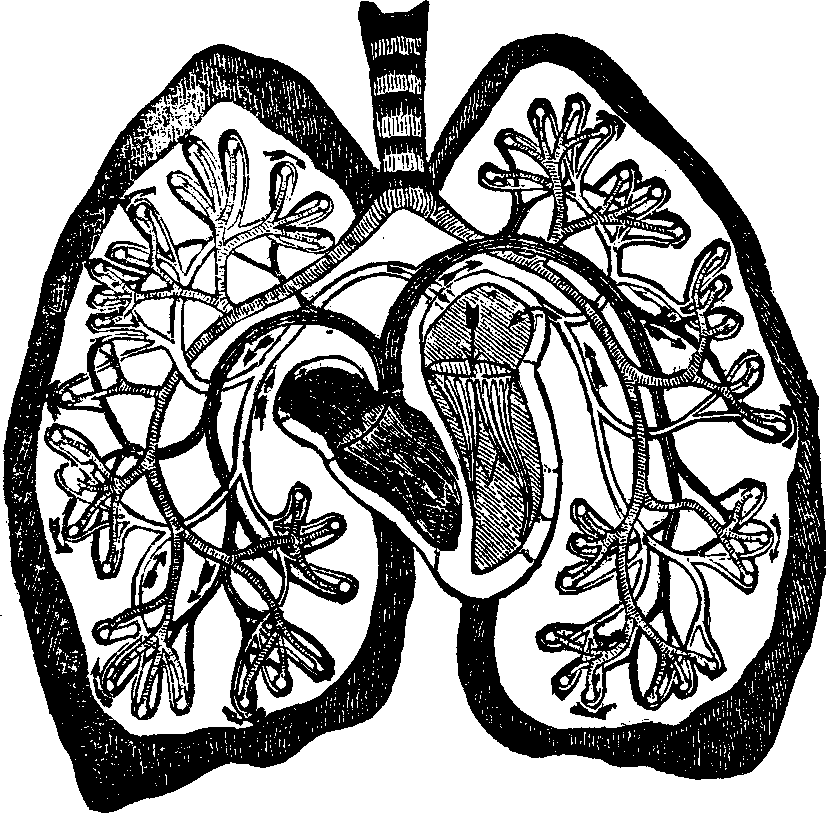

The Spinal Column or backbone, when viewed from the front presents a perpendicular appearance, but a side view shows four distinct curves. The bones composing it are called vertebræ. The body part of a vertebra is light and spongy in texture, having seven projections called processes, four of which are the articular processes, which furnish surfaces to join the different vertebræ of the spinal column. Two are called transverse, and the remaining one is termed the spinous. The transverse [pg 25]and spinous processes serve for the attachment of the muscles belonging to the back. All these processes are more compact than the body of the vertebra, and, when naturally connected, are so arranged as to form a tube which contains the medulla spinalis, or spinal cord. Between the vertebræ is a highly-elastic, cartilaginous and cushion-like substance, which freely admits of motion, and allows the spine to bend as occasion requires. The natural curvatures of the spinal column diminish the shock produced by falling, running or leaping, which would otherwise be more directly transmitted to the brain. The ribs at the sides, the sternum in front, and the twelve dorsal bones of the spinal column behind, bound the thoracic cavity, which contains the lungs, heart, and large blood-vessels.